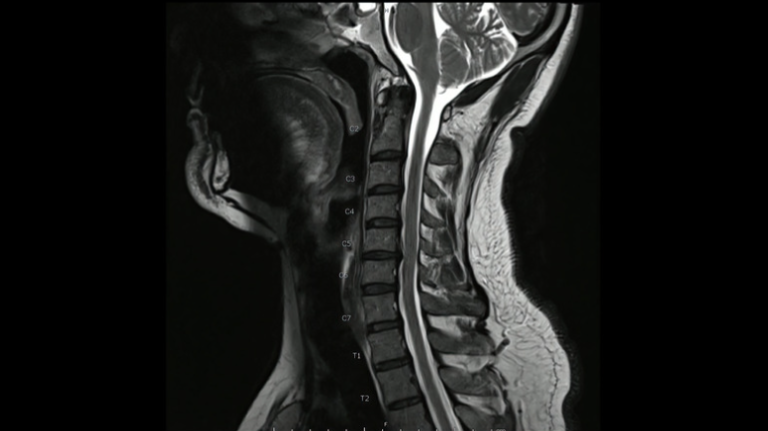

首のMRIで神経の圧迫所見がある場合確定診断します。

頚椎症の診断はヘルニア同様、痛みしびれの範囲、レントゲン、MRIで行います。

また頸椎MRIで脊髄の圧迫と信号変化があると頚髄症を強く考えます。